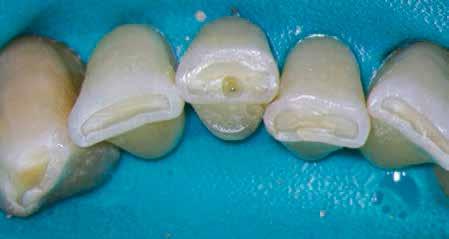

1. a–g. ábrák: A direkt pulpasapkázás lépései. Kiindulási bitewing-felvétel: A meglévő restaurátum közel helyezkedett el a pulpakamrához (a). Kiindulási periapicalis felvétel: Nincs periapicalis elváltozás fennállására utaló jel (b). A pulpaexpozíció (c). A vérzéscsillapítás céljából 20 másodpercen keresztül steril vattagombóccal történő kompressziót követően látható pulpaseb (d). A pulpasapkázás céljából behelyezett anyag, a széli részek tisztázása előtt készült felvétel (e). A röntgenárnyékot nem adó ideiglenes tömés behelyezése után készült felvétel (f). Az első ülés végén a röntgenárnyékot nem adó ideiglenes töméssel ellátott fogról készített röntgenfelvétel (g).

2. ábra: A hat hónapos kontroll alkalmával készített röntgenfelvételen vastag dentinhíd látható a pulpasapkázó anyag alatt.

3. ábra: A hároméves kontroll alkalmával készített röntgenfelvételen megfigyelhető a restaurátum pontos illeszkedése.

4. ábra: A direkt pulpasapkázás lépéseit bemutató videó (https://youtu.be/bfBksF35IjY).

5. ábra: A kalcium-szilikát alapú sealerek klinikai alkalmazását bemutató videó (https://youtu.be/h3p1mZlNUzM).

Esetbemutatás (1.)

A diagnózisunk reverzibilis pulpitis volt. Periapicalis elváltozás jelenlétét nem vélelmeztük. A fogban lévő amalgámtömés eltávolítása során körülbelül egy 3 mm átmérőjű pulpaseb keletkezett a buccalis pulpaszarvnak megfelelően (1. a–g. ábrák) Mivel nem tapasztaltunk jelentős vérzést, és a diagnózisunk reverzibils pulpitis volt, ezért a direkt pulpasapkázás elvégzése mellett döntöttünk.

A kavitást 2,5%-os nátrium-hipoklorit oldattal fertőtlenítettük, majd sűrű konzisztenciájú kalcium-szilikát alapú anyagot (CeraPutty, Meta Biomed) készítettünk elő a direkt pulpasapkázás elvégzéséhez. Az első kezelés végén röntgenárnyékot nem adó ideiglenes töméssel (NexTemp LC, Meta Biomed) zártuk

az üreget annak érdekében, hogy a direkt pulpasapkázásra használt anyag megfelelő pozícióját radiológiailag ellenőrizni tudjuk. A második ülés során kompozit tömőanyagból (Ezfil, Meta Biomed) direkt adhezív restaurátumot készítettünk.

A kezelést követően a beteg tünetmentes volt. A kérdéses fog a kontrollvizsgálatok során végzett szenzibilitástesztekre fiziológiás reakciókat adott. A hat hónapos kontroll alkalmával készített röntgenfelvételen a sérülésnek megfelelően széles dentinhidat észleltünk (2. ábra). A restaurátum a hároméves kontroll során is megfelelőnek bizonyult (3. ábra)